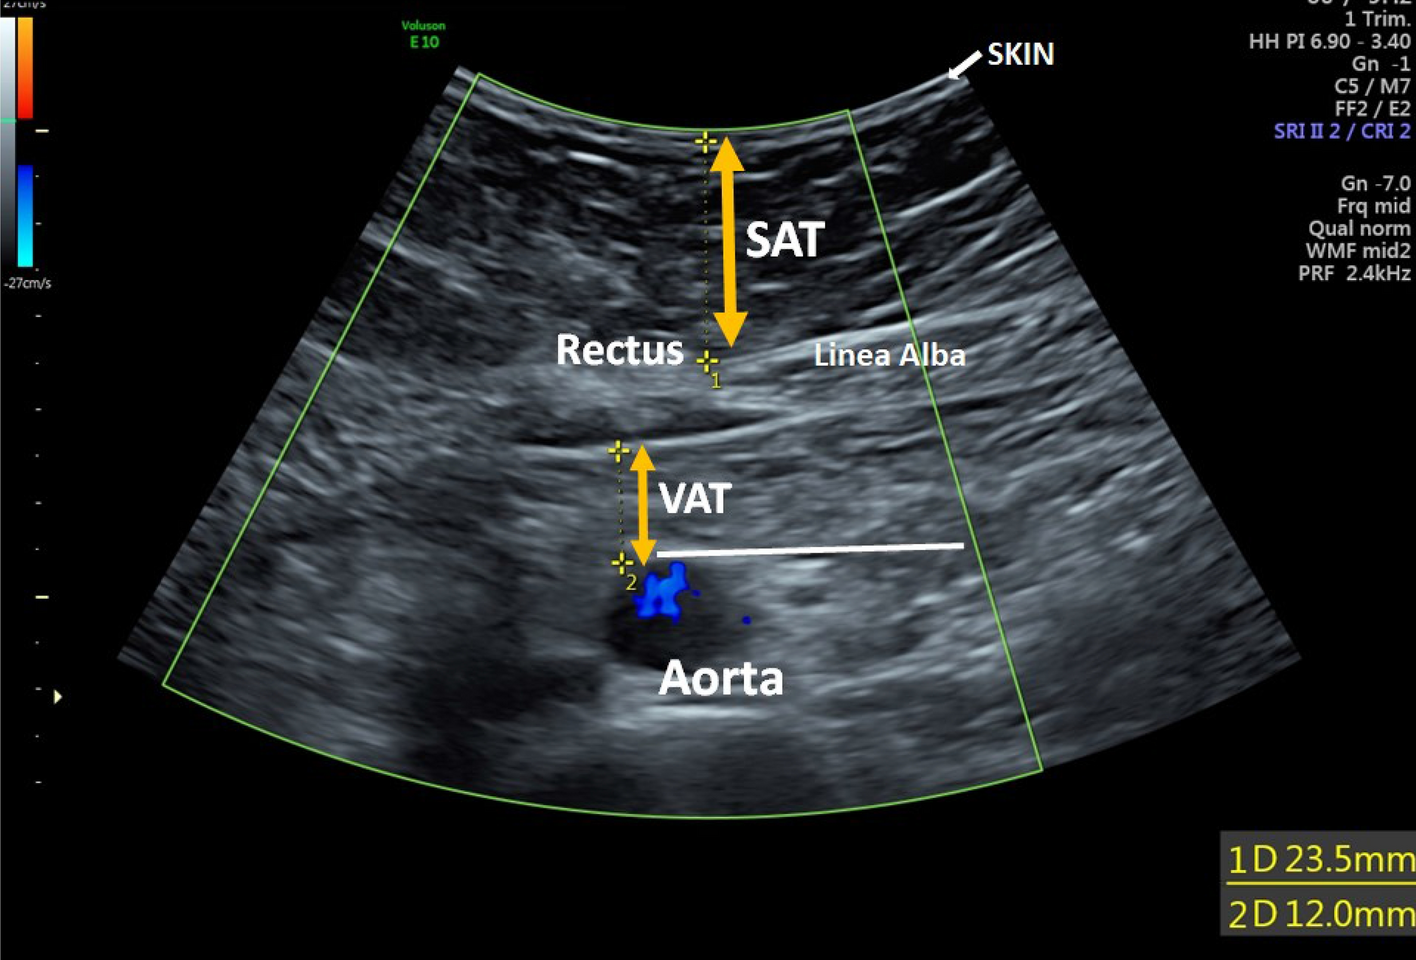

Figure 2

From: Ultrasound estimated subcutaneous and visceral adipose tissue thicknesses and risk of pre-eclampsia

Adipose tissue measurement taken 10 cm above the level of the umbilicus. The subcutaneous adipose tissue (SAT) thickness measured from the inner border of the skin down to line alba. The visceral adipose tissue (VAT) thickness measured from the posterior edge of the line alba to the anterior aortic wall.